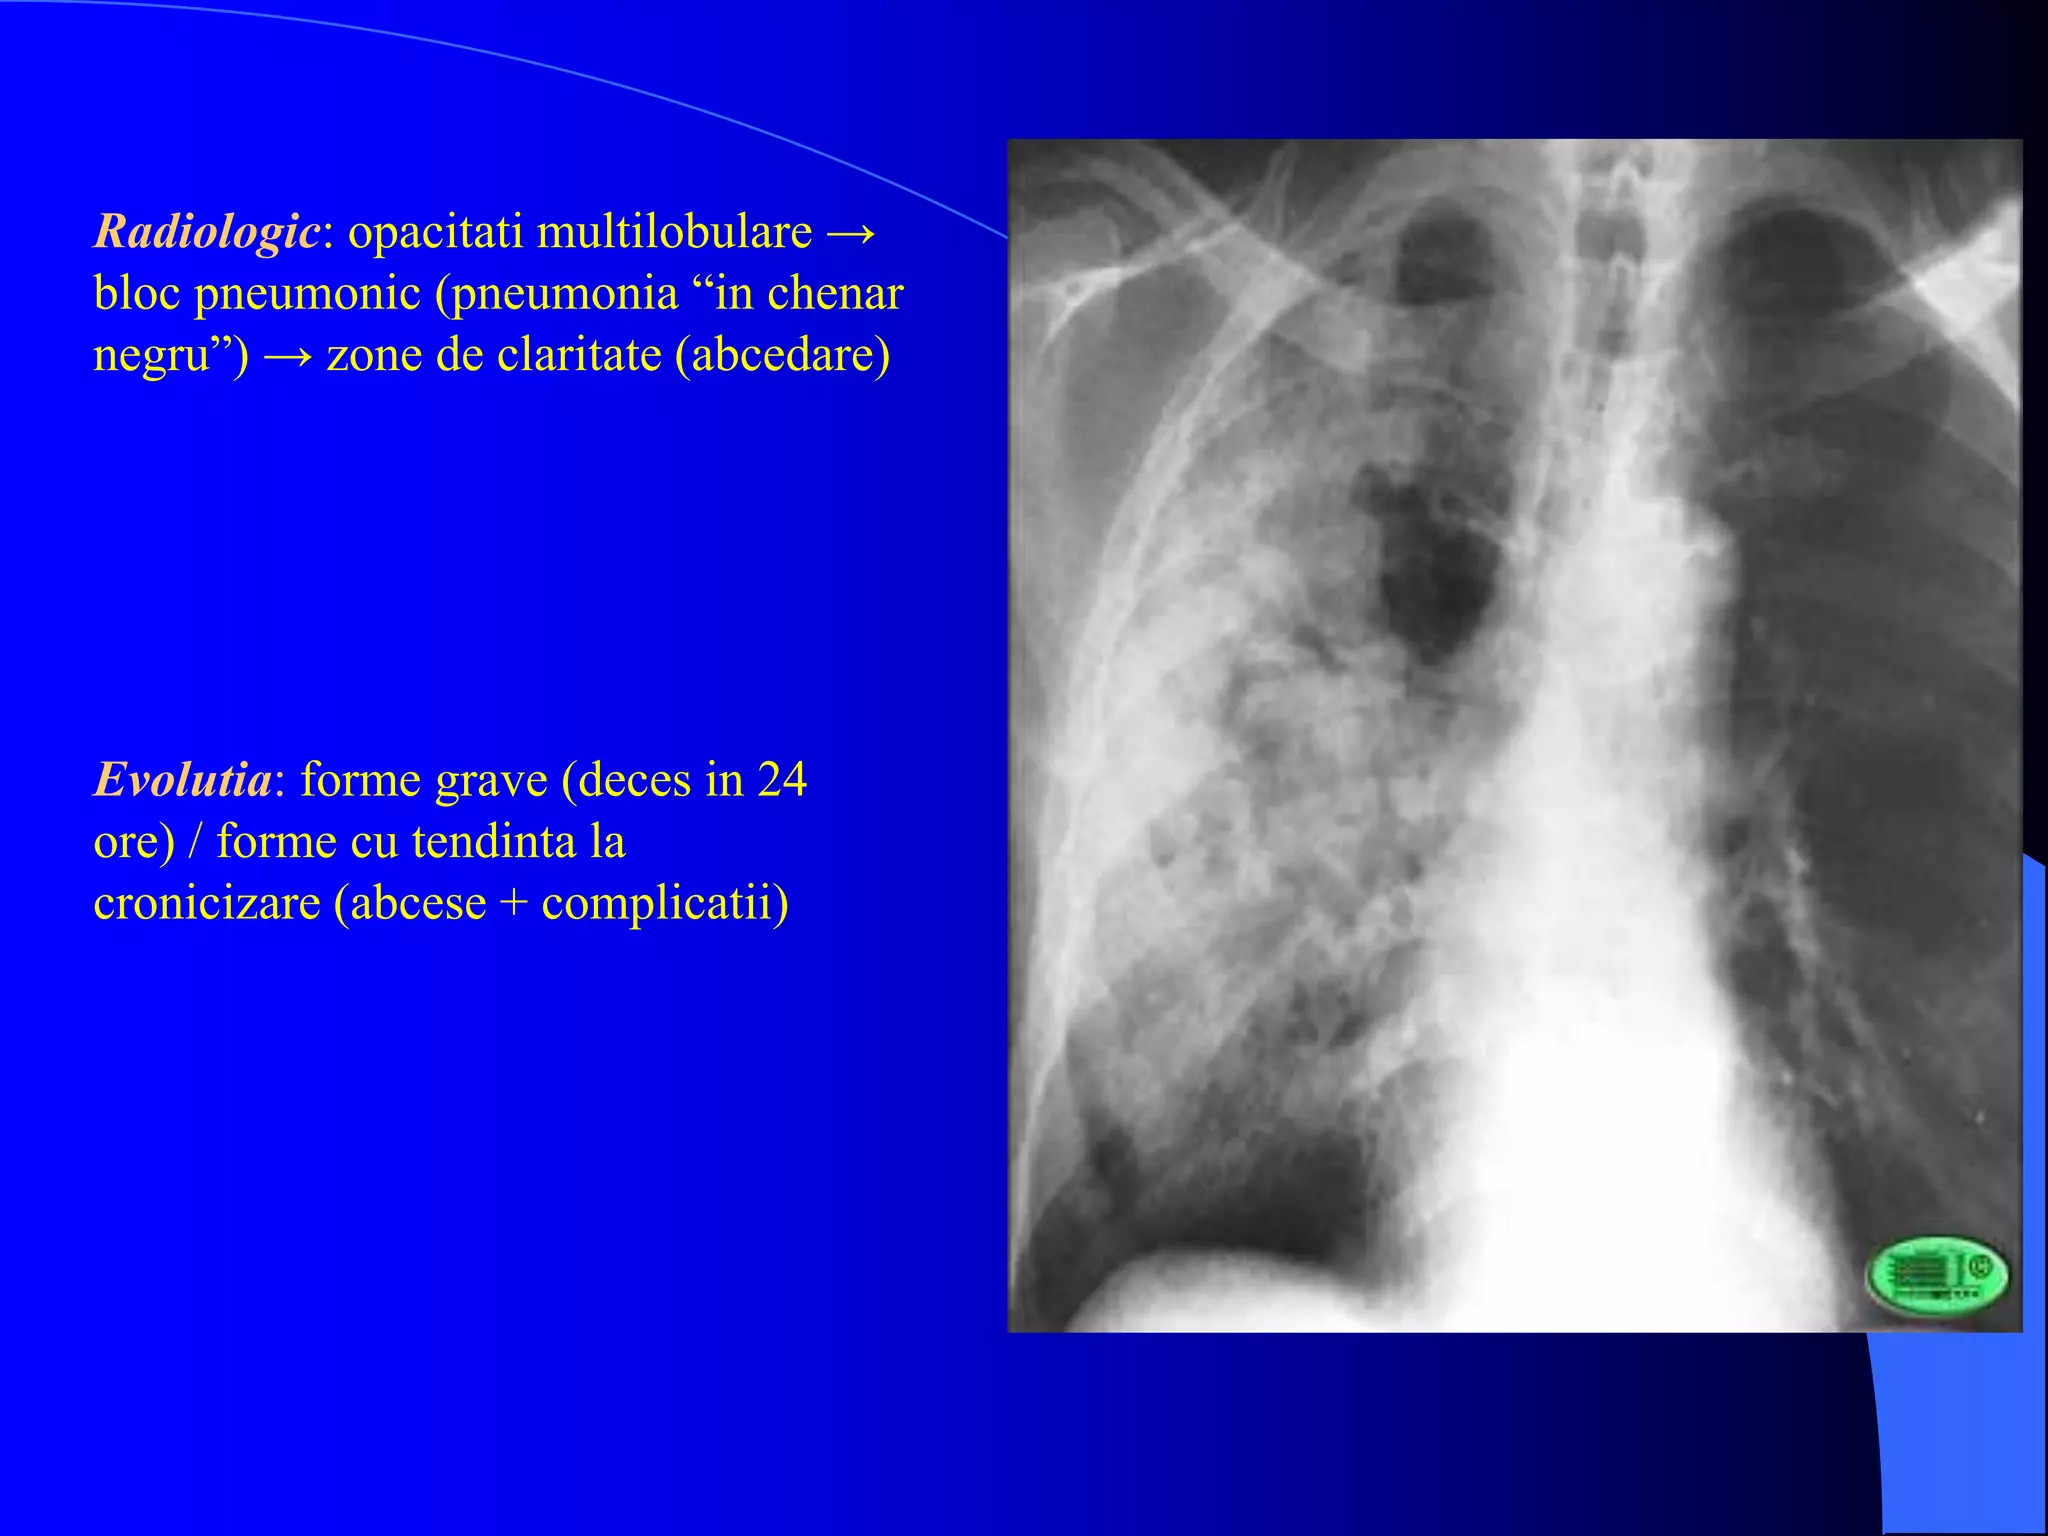

Radiologic: opacitati multilobulare →

bloc pneumonic (pneumonia “in chenar

negru”) → zone de claritate (abcedare)

Evolutia: forme grave (deces in 24

ore) / forme cu tendinta la

cronicizare (abcese + complicatii)